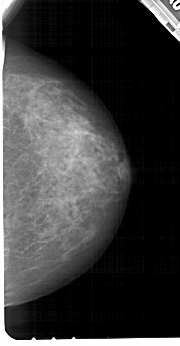

A_1211_1.RIGHT_MLO

RIGHT_MLO LINES 5491 PIXELS_PER_LINE 2761 BITS_PER_PIXEL 12 RESOLUTION 43.5 NON_OVERLAY